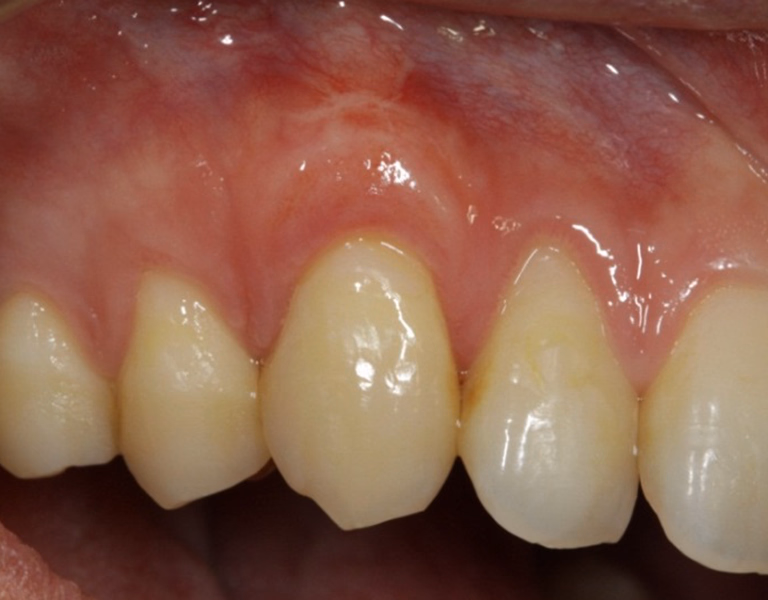

治療前後写真

治療前

治療後

40代 女性

歯茎が下がっている

治療内容

- ① 歯周組織検査

- ② 歯周初期治療(プラーク・歯石除去 ブラッシング指導)

- ③ 歯周形成外科治療

マイクロスコープを用いて結合組織移植術を行う

3ヶ月(手術当日+月1回の経過観察を3回)

440,00 円(税込・自費診療、保険適用外)

- 術後の腫脹・疼痛・出血

- 術後の感染

- 移植組織の壊死

医院コメント

定期メンテナンスにより長期安定を目指します。